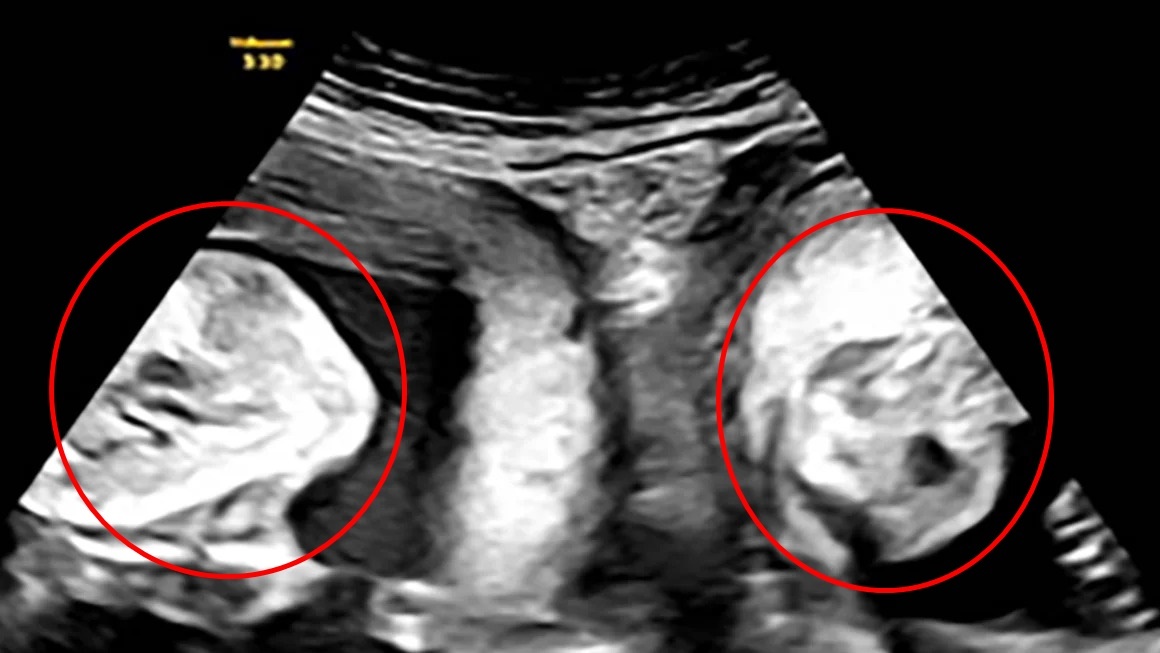

Em bé chào đời với 3 vòng dây rốn quấn quanh cổ. Ảnh: BVCC.

Sau 10 phút, ca mổ đã diễn ra thuận lợi. Bé trai nặng 3 kg chào đời an toàn, trên cổ có 3 vòng dây rốn quấn quanh.

Theo các bác sĩ Bệnh viện Sản Nhi Nghệ An, tình huống dây rốn quấn cổ là hiện tượng sinh lý bình thường, dễ bắt gặp trong 3 tháng cuối của thai kỳ. Điều này thường sẽ không gây ảnh hưởng đến thai.

Tuy nhiên, nếu dây rốn quấn cổ quá nhiều vòng hoặc quá chặt, quá trình vận chuyển máu và dinh dưỡng nuôi thai nhi sẽ bị cản trở, dẫn đến nguy cơ thai nhi sinh ra nhẹ cân, thiếu máu, thậm chí là tử vong trong bụng mẹ…